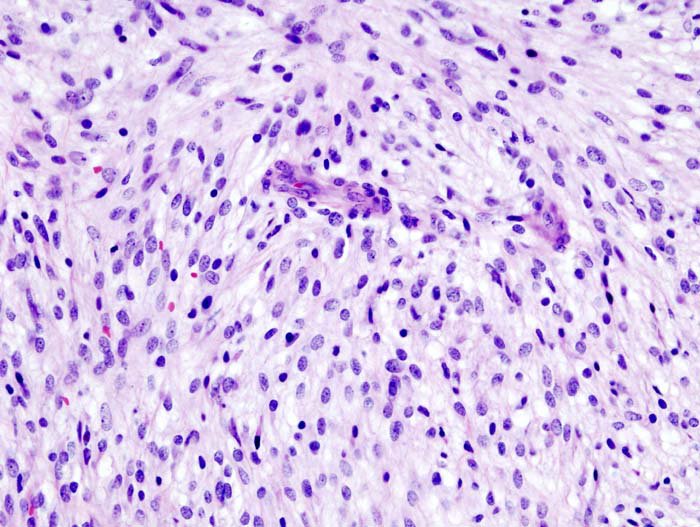

Pathology Outlines - Leiomyoma-general

www.pathologyoutlines.com

www.pathologyoutlines.com

leiomyoma leiomyomas deficient fh pathology outlines uterus diagnosed recurrent

Pathology Outlines - Leiomyoma-general

www.pathologyoutlines.com

www.pathologyoutlines.com

leiomyoma pathology outlines hydropic uterus

Pathology Outlines - Leiomyoma-general

www.pathologyoutlines.com

www.pathologyoutlines.com

leiomyoma pathology uterus apoplectic outlines

Pathology Outlines - Myxoid Leiomyoma

www.pathologyoutlines.com

www.pathologyoutlines.com

leiomyoma myxoid pathology outlines

Pathology Outlines - Leiomyoma-general

www.pathologyoutlines.com

www.pathologyoutlines.com

leiomyoma pathology myxoid outlines uterus

Pathology Outlines - Myxoid Leiomyoma

www.pathologyoutlines.com

www.pathologyoutlines.com

myxoid leiomyoma smooth cells muscle